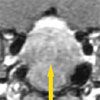

An MRI scan of the brain is shown here.

Galactorrhea, headaches, a large mass in the sella turcica, an elevated prolactin level, and a low LH level in a young woman in whom all other results of an endocrine workup are normal strongly suggest a macroadenoma of the pituitary gland (A).